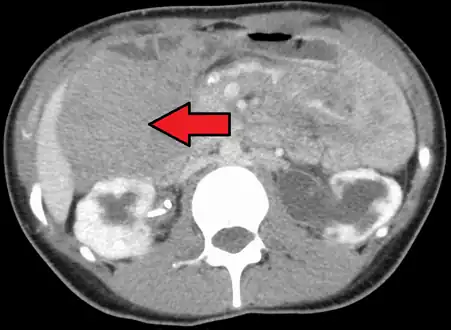

| Desmoid tumor as seen on CT scan | |

Aggressive fibromatosis or desmoid tumor is a rare condition. Desmoid tumors arise from cells called fibroblasts, which are found throughout the body and provide structural support, protection to the vital organs, and play a critical role in wound healing. These tumors tend to occur in women in their thirties, but can occur in anyone at any age. They can be either relatively slow-growing or malignant. However, aggressive fibromatosis is locally aggressive and can cause life-threatening problems or even death when they compress vital organs such as intestines, kidneys, lungs, blood vessels, or nerves. Most cases are sporadic, but some are associated with familial adenomatous polyposis (FAP). Approximately 10% of individuals with Gardner's syndrome, a type of FAP with extracolonic features, have desmoid tumors.[1]

Desmoid tumors may be classified as extra-abdominal, abdominal wall, or intra-abdominal (the last is more common in patients with FAP). It is thought that the lesions may develop in relation to estrogen levels or trauma/operations.